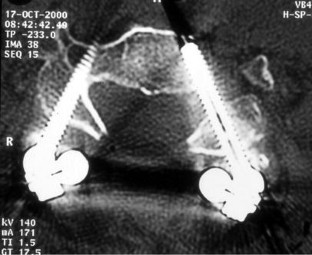

Fig. 1